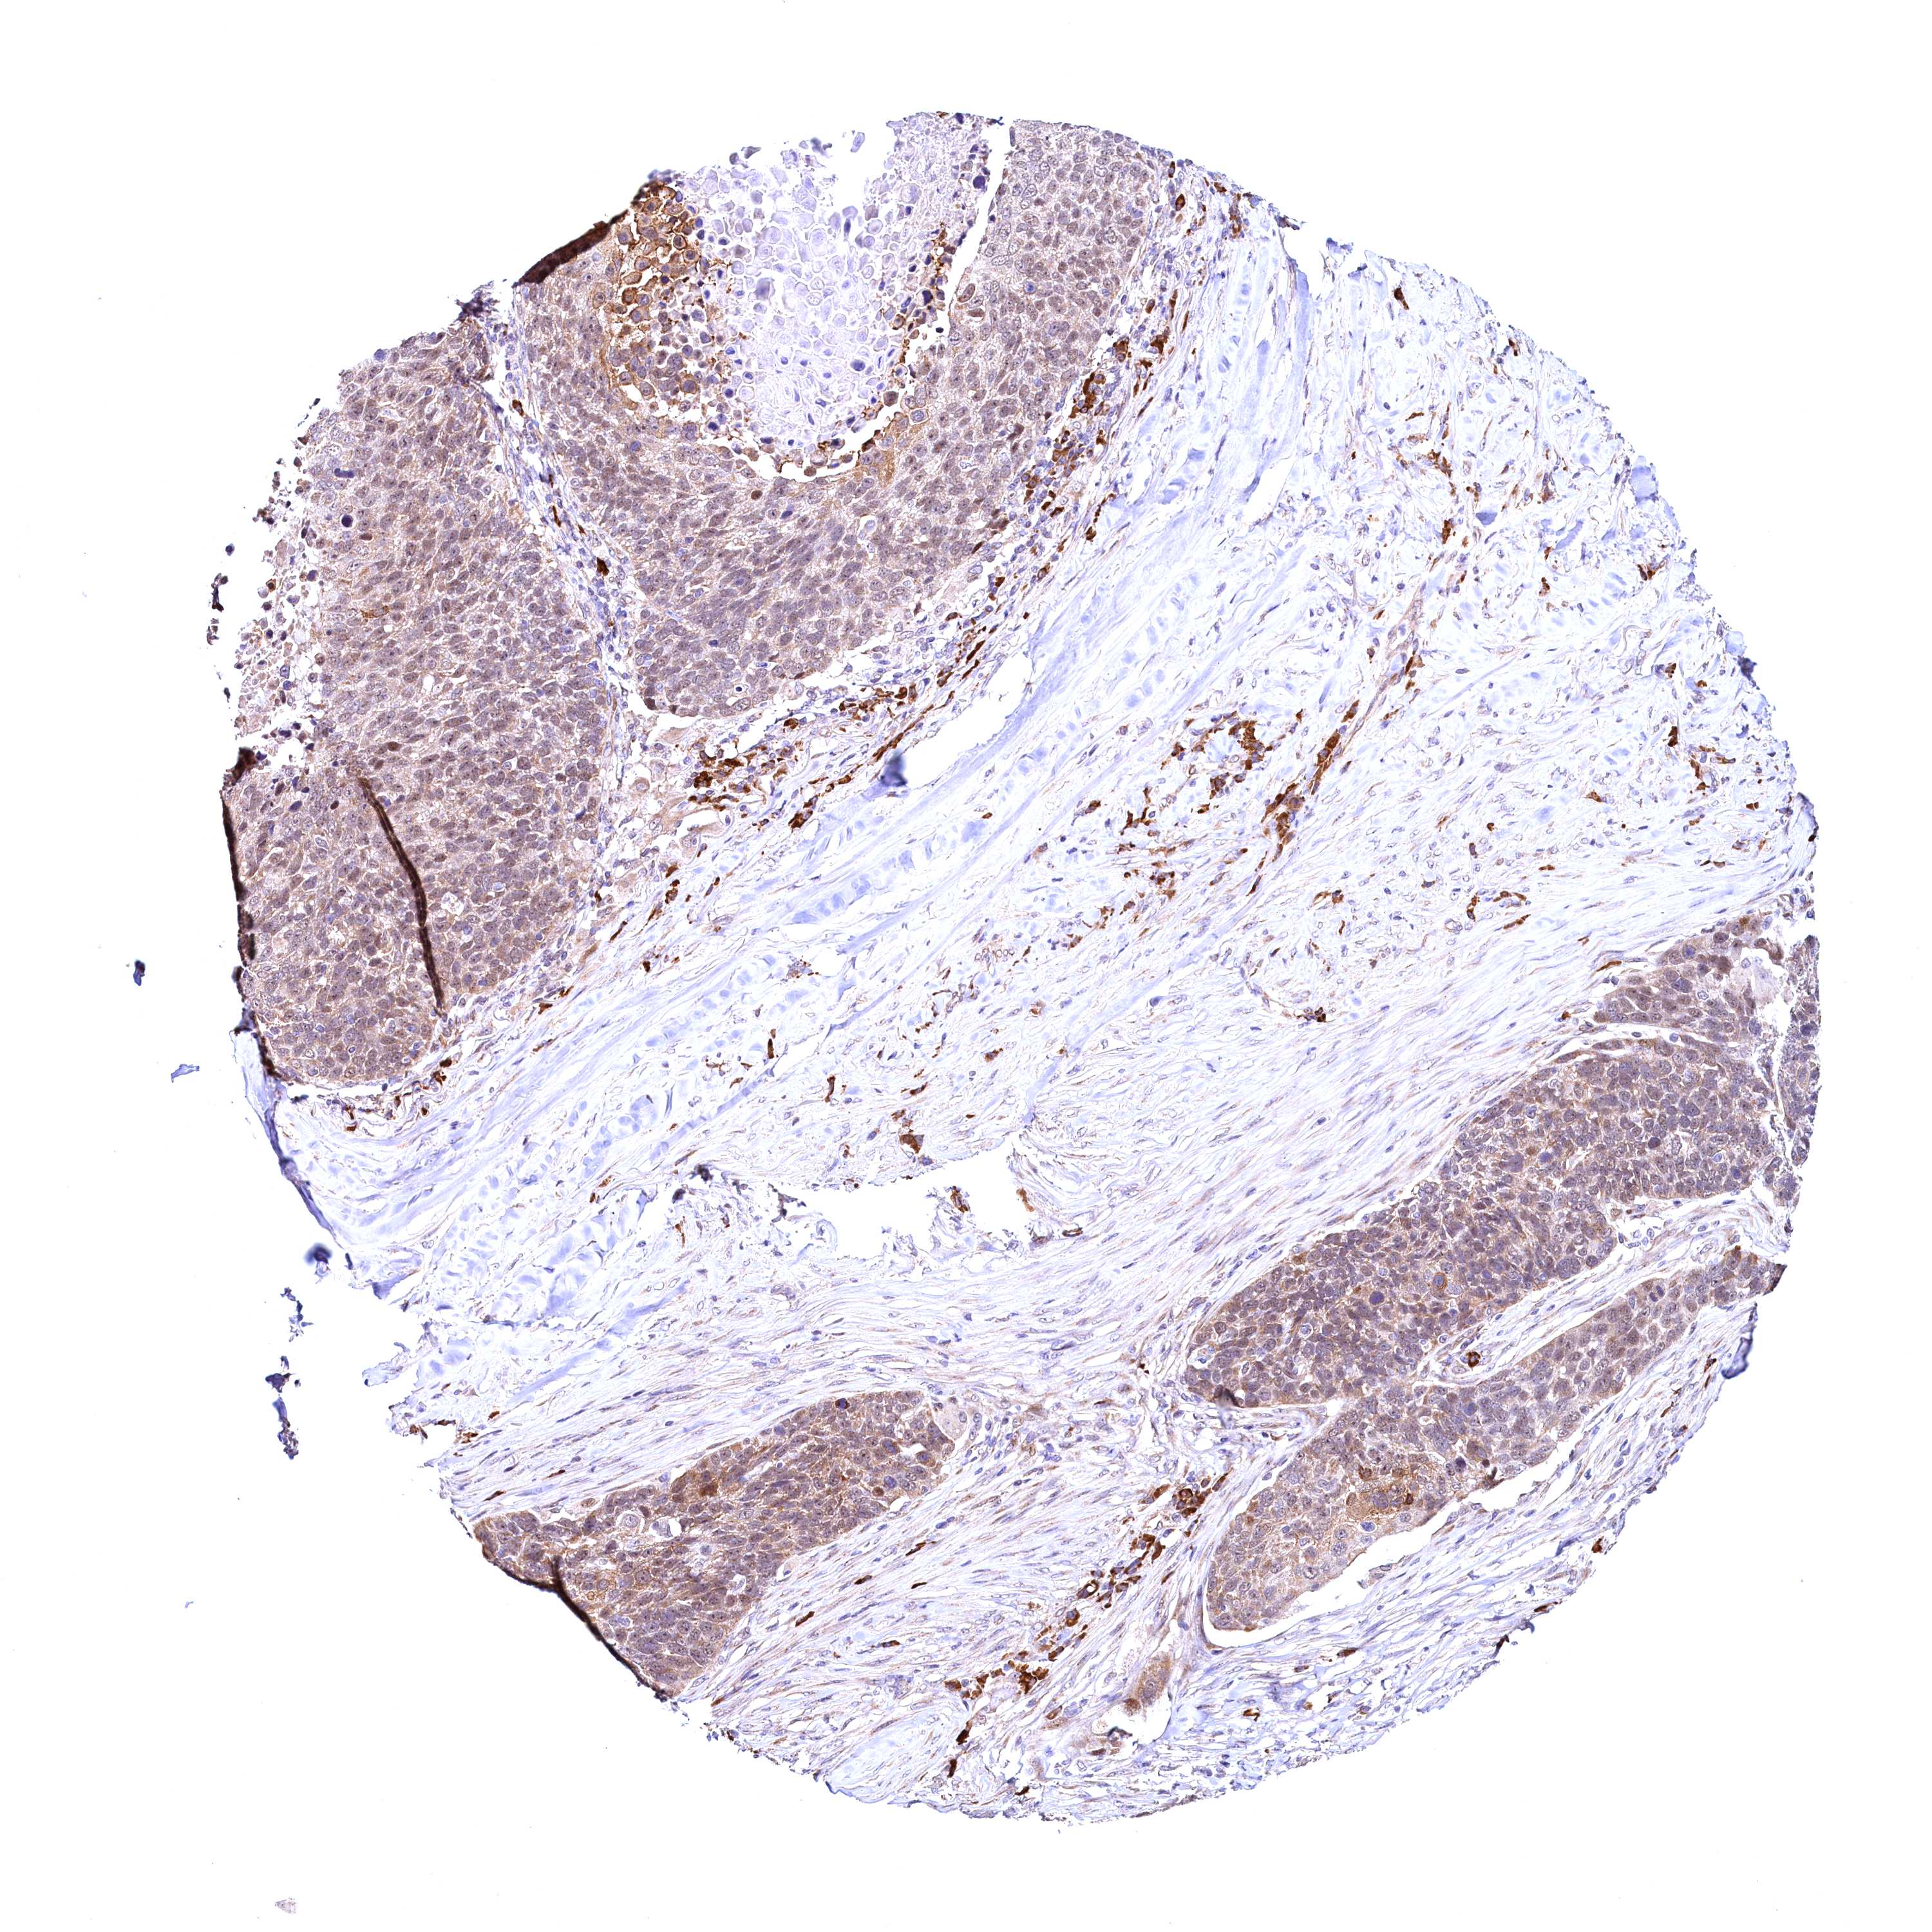

CANCER LUNG CANCER Show tissue menu

LUAD TCGA LUAD VALIDATION LUSC TCGA LUSC VALIDATION PROTEIN LUAD CPTAC PROTEIN LUSC CPTAC PROTEIN EXPRESSION

ANTIBODIES

AND

VALIDATION